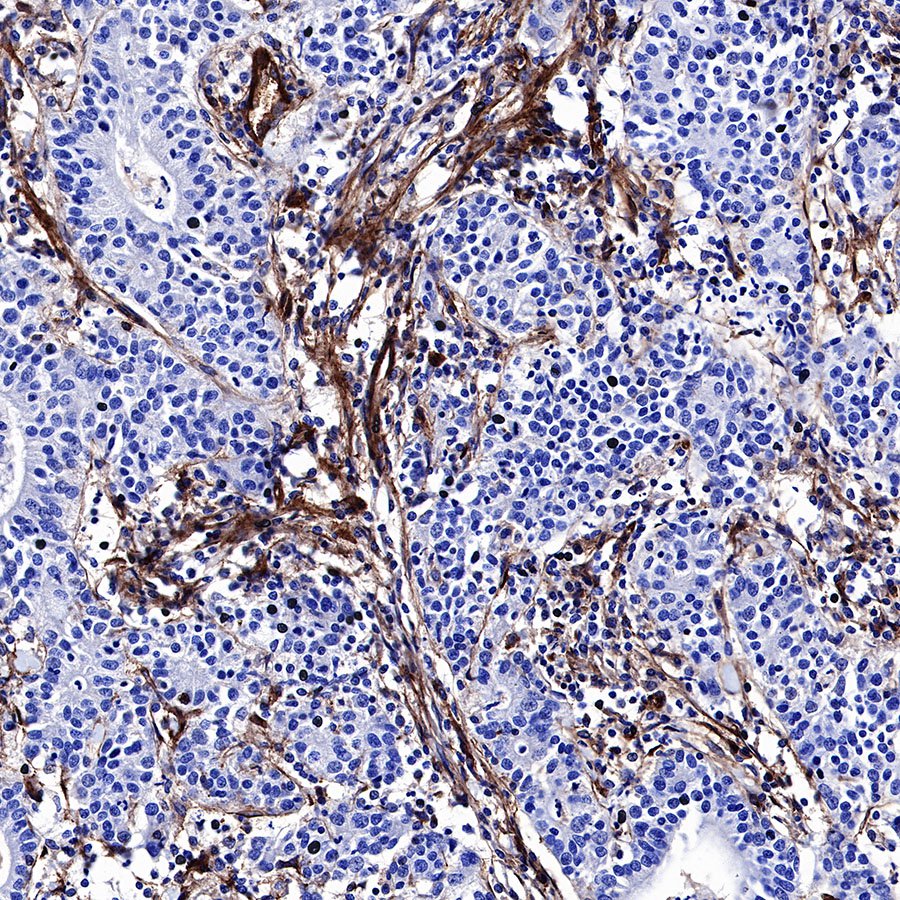

IHC shows positive staining in paraffin-embedded human gastric cancer. Anti-CD39 antibody was used at 1/500 dilution, followed by a HRP Polymer for Mouse & Rabbit IgG (ready to use). Counterstained with hematoxylin. Heat mediated antigen retrieval with Tris/EDTA buffer pH9.0 was performed before commencing with IHC staining protocol.